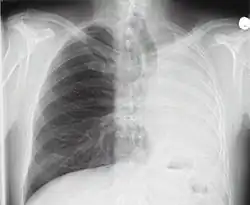

Bei den radiographischen Verfahren (auch als „konventionelles Röntgen“ bezeichnet) werden Bereiche des Körpers des Patienten aus einer Richtung mit Röntgenstrahlung durchstrahlt. Auf der Gegenseite wird die Strahlung mit geeigneten Materialien registriert und in ein Bild umgewandelt. Dieses zeigt die im Strahlengang liegenden Gewebe in der Projektion: Knochen absorbieren mehr Strahlung als Weichteile und werfen daher Schatten; luftgefüllte Gewebe wie die Lunge sind relativ durchlässig, sodass dahinter eine höhere Strahlenintensität registriert wird. Da verschiedene Strukturen sich meist im Strahlengang überlagern, ist es oft hilfreich, mehrere Bilder aus unterschiedlicher Projektionsrichtung anzufertigen.

- Röntgen Thorax: Übersichtsaufnahme von Herz, Lunge und Brustkorb